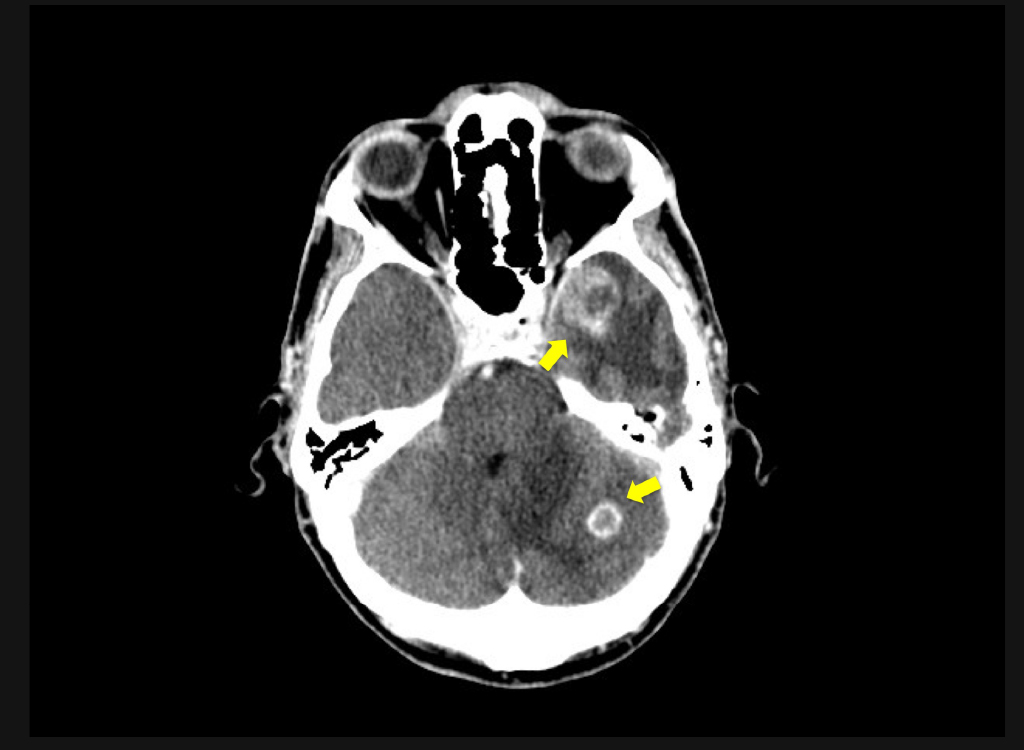

El paciente acudió a urgencias por cefalea hemicraneal persistente que no cedía con analgésicos. A la exploración neurológica se le halló obnubilado sin clara focalidad neurológica por lo que se solicitó un TC craneal que mostró dos imágenes sugestivas de metástasis (Figura 1), con edema perilesional y efecto masa. Se realizó un TC torácico por imagen sugestiva de neoplasia en radiología simple, que mostró una lesión en parénquima pulmonar de 33x26 mm de bordes irregulares y contornos espiculados, situada en el segmento apical posterior del lóbulo superior izquierdo, la cual contacta la cisura. Imagen muy sugestiva de neoplasia primaria de pulmón (Figura 2).